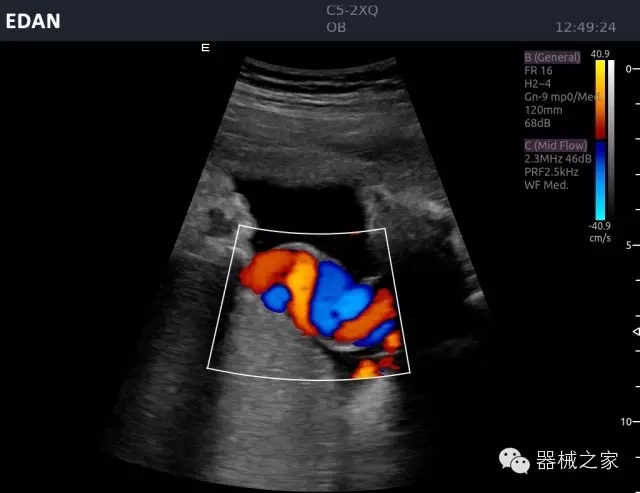

經(jīng)典產(chǎn)品:Acclarix AX8

臨床圖片賞析

睪丸低速血流

臍帶血流